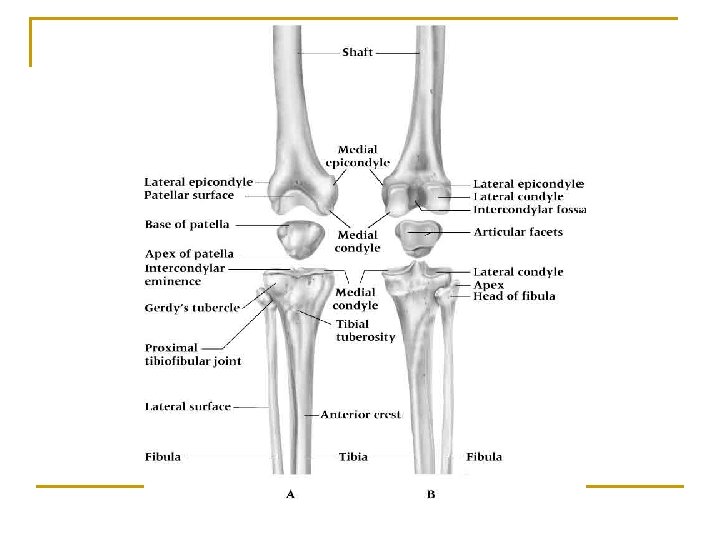

Knee Structures n n Hinge Joint Stability comes from ligamentous support Femur, tibia, fibula, patella Menisci ~ 2 oval fibrocartilages